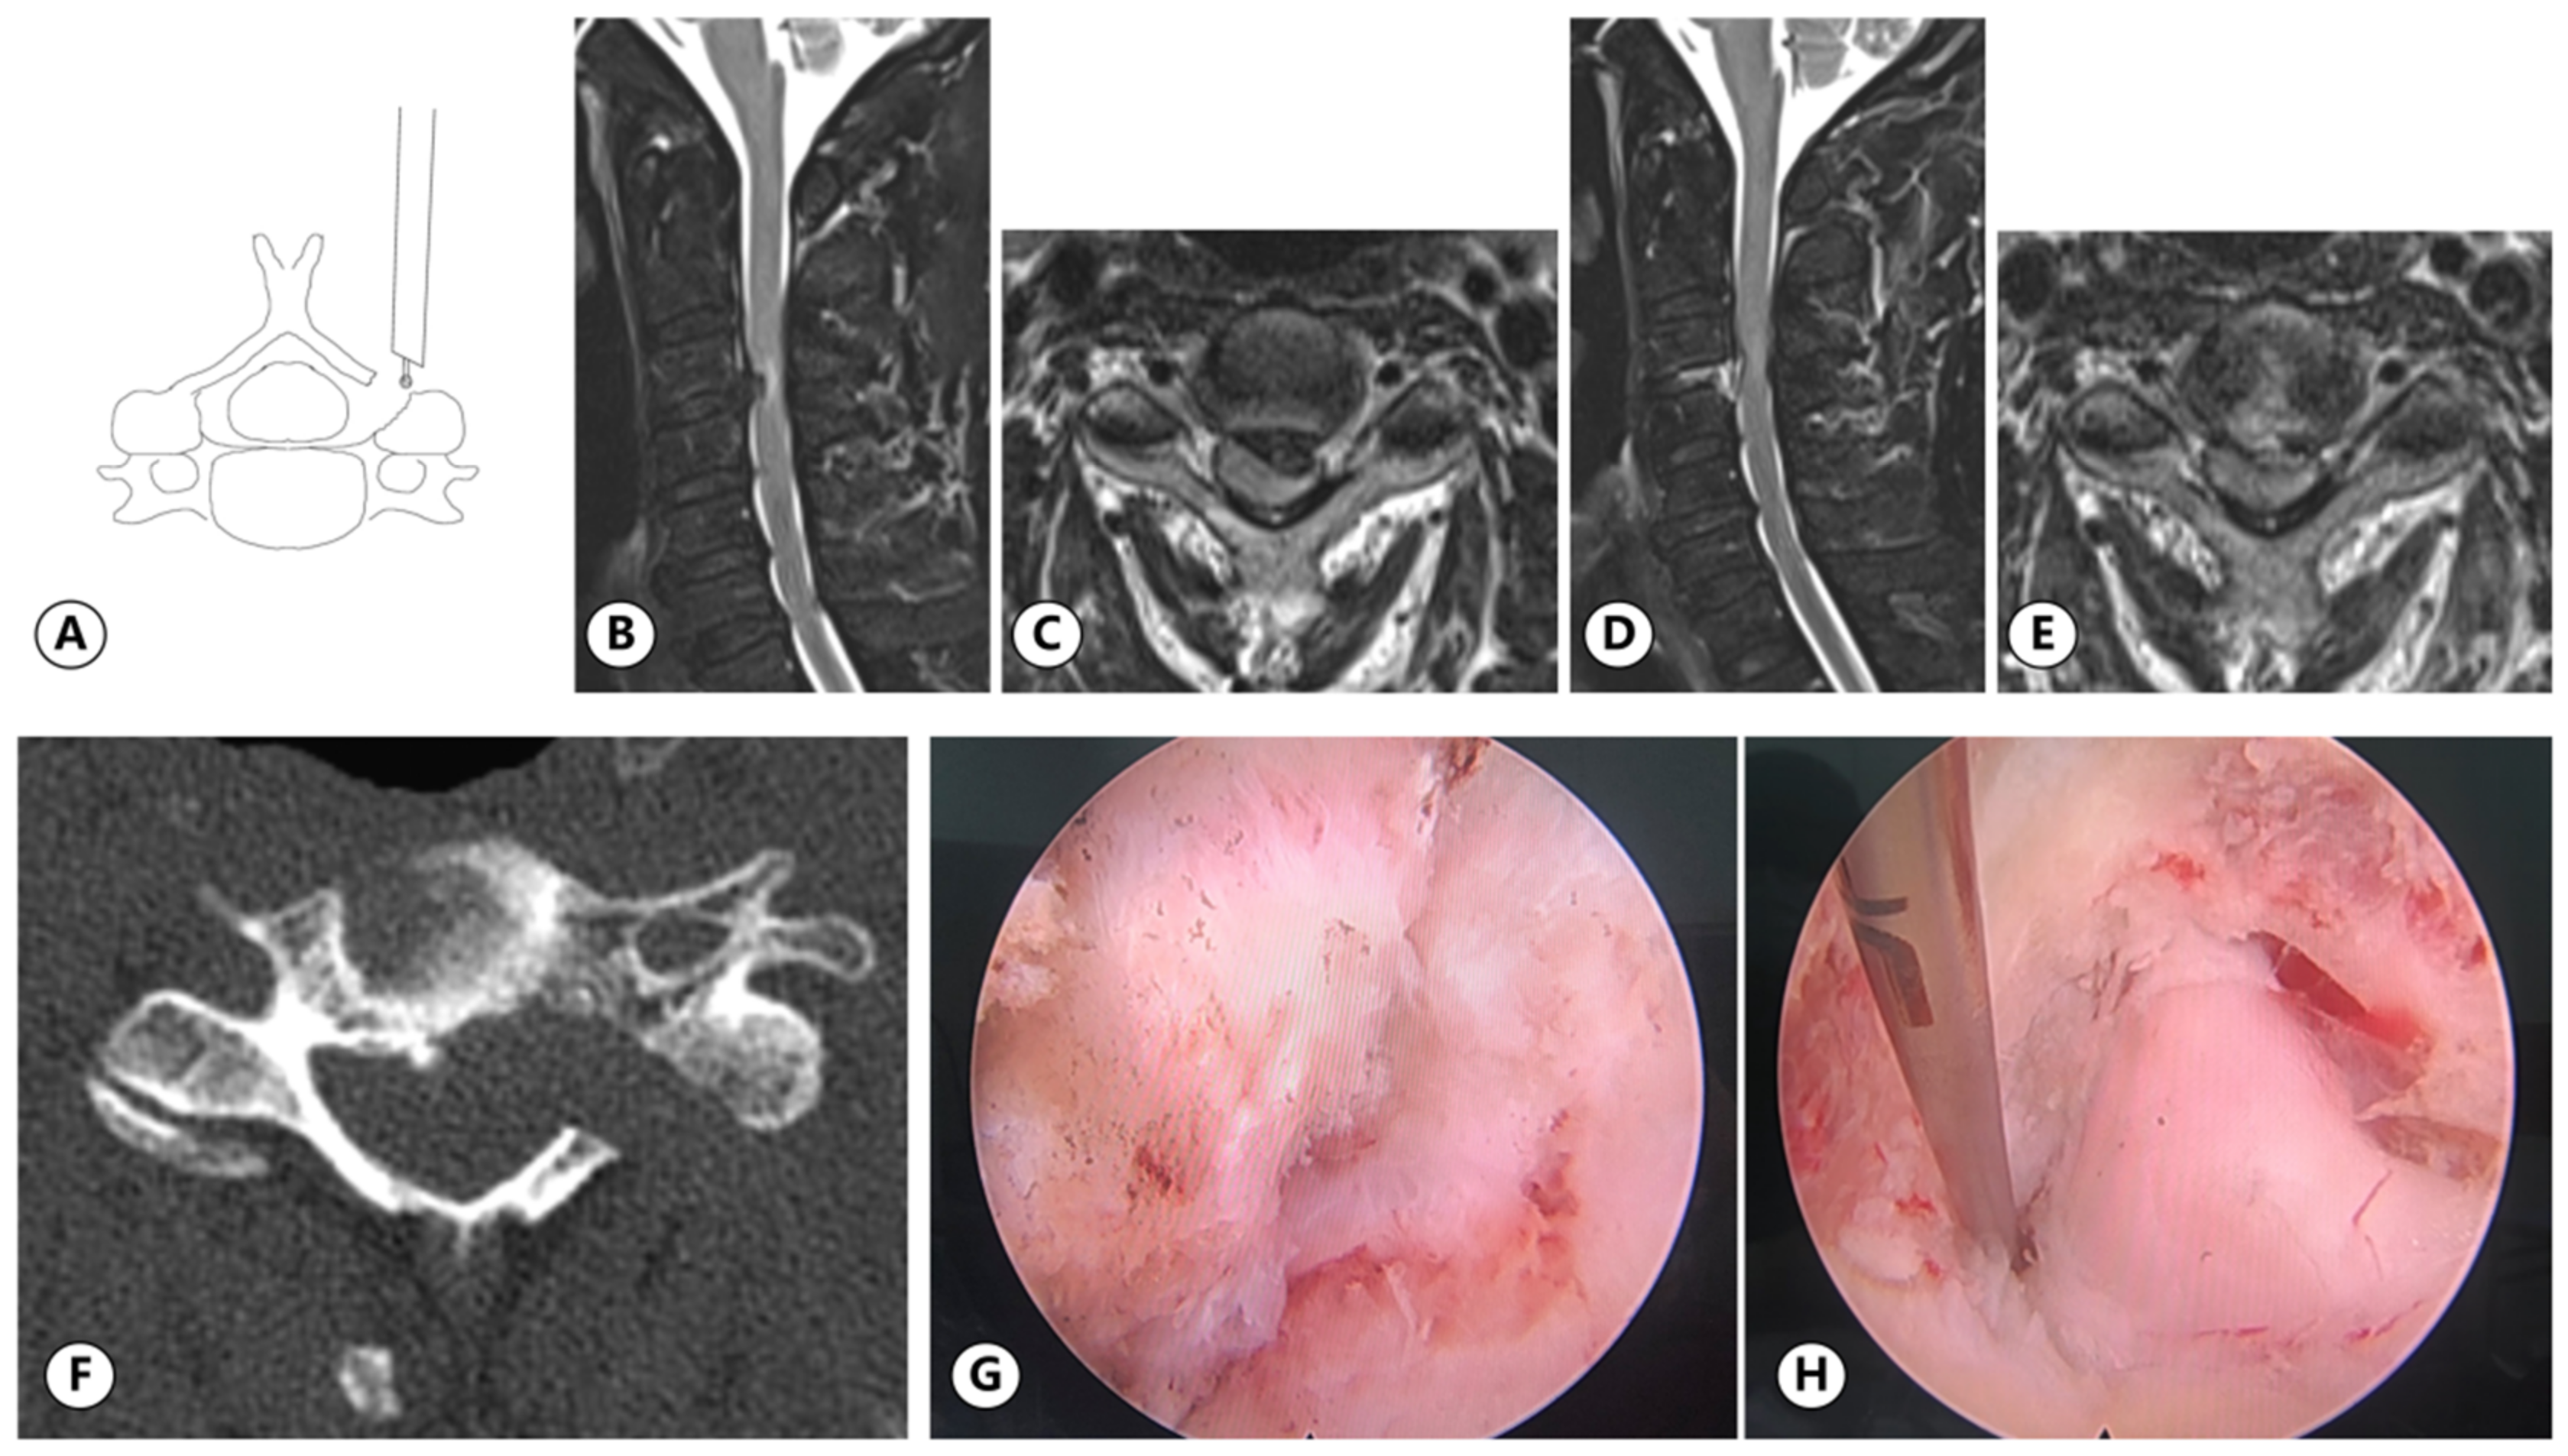

2.3.1. UBE

2.3.2. PE